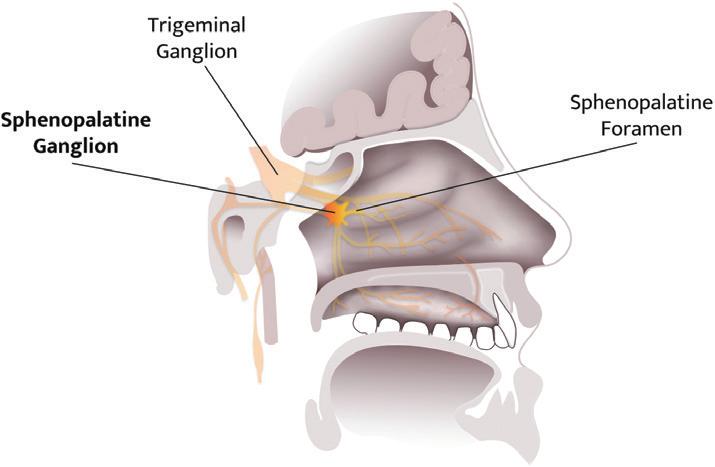

Addressing CNS Therapies Through Nose-to-Brain Pathways

Alain Regard, Technology Product Manager;

Raphaële Audibert, Marketing Category Manager – Ear Nose Throat; and Audrey Chandra, Marketing Category Manager

Nemera